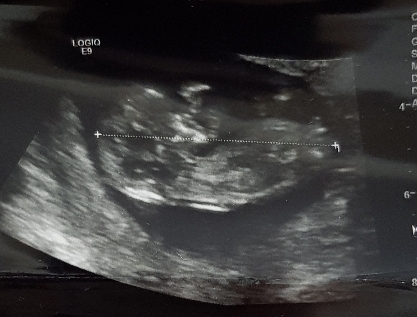

جنسیت نی نی

علائمت چیه

به نظرم اصلا اين علايم درست نيستن، واسه هركس يه طوريه فقط به سونو اعتماد كنيد،من علايمم دختر ب ...

مثلا چه علائمی اخه من دختره ولی همه میگن تو بچت پسره نمودونم